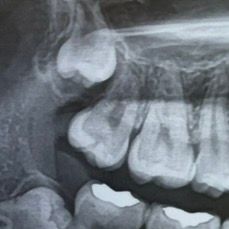

또 이 사이부분에 충치인것처럼 보이나요..?

• 2번 째 사진

기존치료한걸 다 제거하고 다시 치료를 해야되기 때문에 레진보다는 인레이 치료를 권유합니다. 아래 사진에도 치아 사이에 충치가 잇는것같습니다.

2. 사이 충치 맞을 것 같습니다